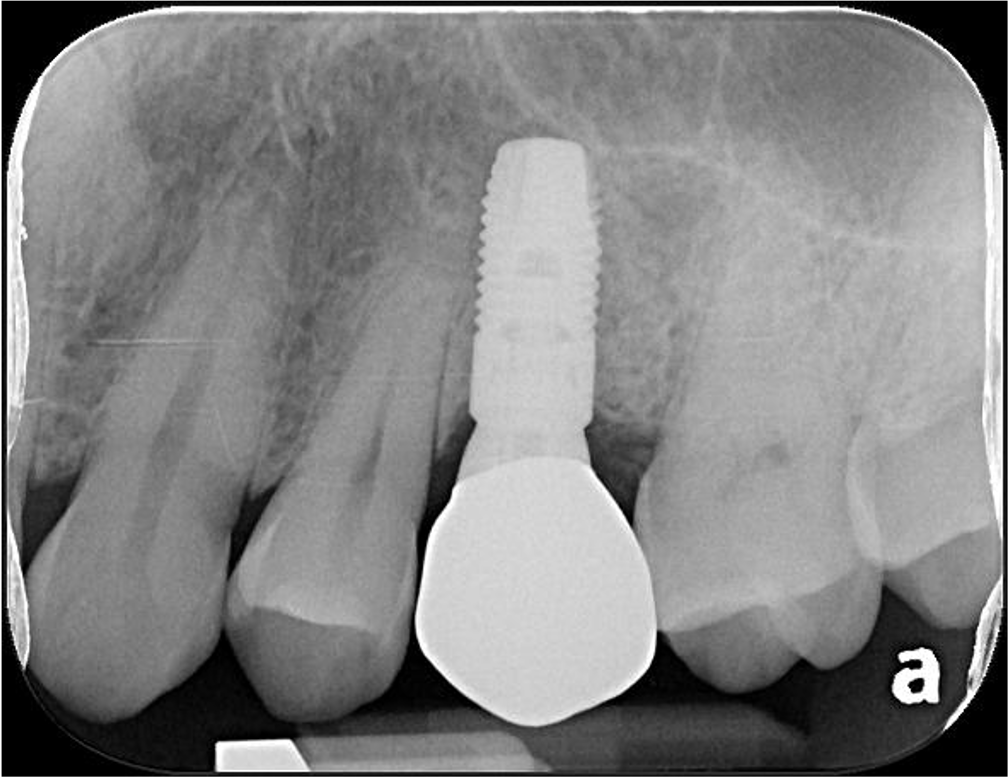

植牙後X光

治療後X光,穩合度良好